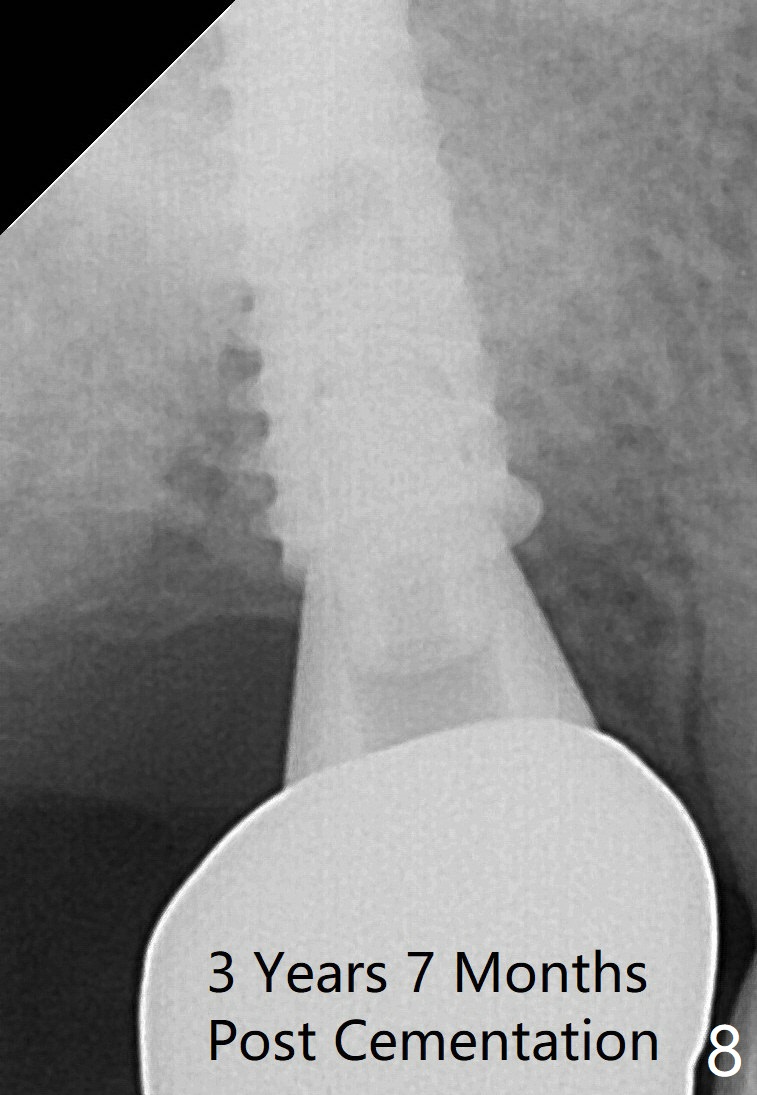

The edentulous ridge at the site of #2 is wide. Magic split is used to gain access, test bone density and start osteotomy for 9 mm (gingival level). A 1.6 mm drill is used to extend the osteotomy for depth of 13 mm. The osteotomy position and trajectory is confirmed with a parallel pin (Fig.1), which is ideal. The remaining osteotomy is finished with Magic Expanders from 3 to 4.3 mm for 15 mm. The trajectory is confirmed again with insertion of a 4.5x11 mm dummy implant at the depth of 15 mm (Fig.2). When a definitive IBS implant (5x13 mm) is placed with insertion torque >45 Ncm, the distal coronal end is not subcrestal (Fig.3-5). As the implant is placed deeper, it started to lose primary stability. When a pair abutment is placed, it keeps turning. Finally a healing abutment (6x3 mm) is placed unstable. In brief, taking several X-ray films help control osteotomy and implant position and trajectory. The implant is unstable 7 months postop (Fig.6). With local anesthesia, the implant is placed deeper by 1 mm with apparent increase in torque and a 6x4 healing abutment placed. The implant is stable 11 months postop. With 5.5x4(4) mm abutment placed, impression is taken. PA and BW will be taken after cementation of the crown. There is no bone loss 9 months post cementation (Fig.7). Return to Upper Molar Immediate Implant, 18-20, 29,30 Xin Wei, DDS, PhD, MS 1st edition 01/09/2017, last revision 08/15/2021